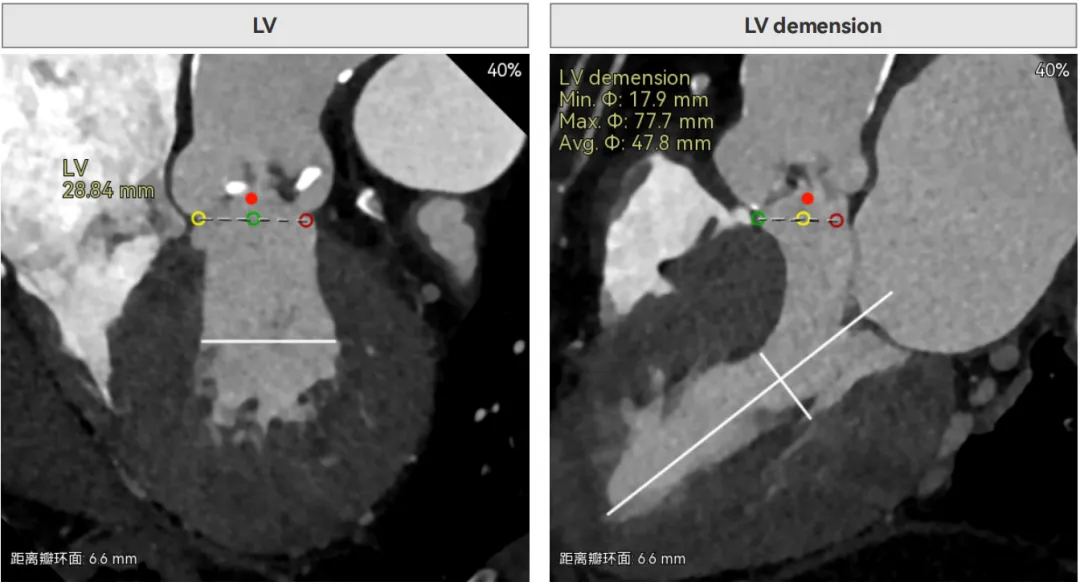

左室内径较小,但合并轻度反流,低循环崩溃风险,室间隔膜部长度<3mm,有一定术后起搏器植入风险。